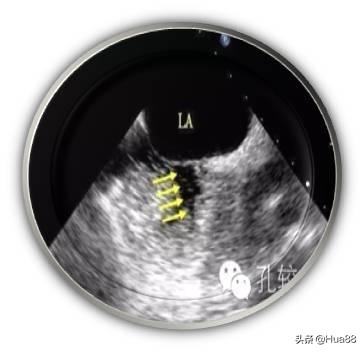

相关检查 医生如怀疑或排查患者是否存在卵圆孔未闭,通常会完善以下检查。由于超声心动图可以直观地显示房间隔解剖结构及心脏内血流分流情况,因此超声心动图是卵圆孔未闭的最 佳诊断检查。 临床上常用的超声心动图包括经胸超声心动图(TTE)、经食管超声心动图(TEE)和经颅多普勒超声声学 造影(cTCD)。 经胸超声心动图(TTE) 性价比高,操作简单、无痛苦,但该检查会受到肥胖和肺气过多等因素的干扰,检出率不高,且难以准确测 量未闭的卵圆孔大小,一般应用于儿童及部分成年人。 经胸超声心动图声学造影(cTTE)可以提高检出率,了解患者有无心脏内血液异常分流。操作时需要静脉注 射声学造影剂。 经食管超声心动图(TEE) 是诊断卵圆孔未闭的“金标准”和首选方法。该检查可以指导医生对卵圆孔未闭进行分类,从而指导治疗。 该检查属于半创伤性检查,操作过程中患者比较痛苦,类似于胃镜检查,插管会造成患者恶心、呕吐等不 适。检查前后患者须禁食、禁水。 经食管超声心动图声学造影(cTEE)亦可用于判断心脏内血液异常分流情况。 此外,三维经食管超声心动图(三维TEE)能够为二维TEE图像提供有力补充,帮助医生了解实时未闭卵圆 孔的状态,更有利于指导治疗。 经颅多普勒超声声学造影(cTCD) 简单、无创、安全。检查心脏内血液有无分流的一种常用方法,但是不能定性诊断卵圆孔未闭。作为卵圆孔 未闭筛查的一种方法,通常需要进一步进行经胸超声心动图(TTE)、经食管超声心动图(TEE)等检查作 为补充。 心导管检查、对比分析双源CT冠状动脉成像和心脏磁共振成像(MRI)可以发现卵圆孔未闭,但费用较高, 敏感性相对较差,临床较为少用。

介入封堵术是一种在局麻下进行的微创手术,手术过程中患者是清醒的,具有痛苦小、恢复快的特点。一般 术后12~24小时就可以下床活动。 其原理是通过大腿根部的股静脉将一根导管送入右心房,穿过未闭卵圆孔至左心房,释放专用封堵器,进而 关闭卵圆孔,从而达到根治的目的。 但介入封堵术并不适用于所有患者,具有严格的适应证及禁忌症要求,行封堵术前医生会进行全面评估,再 征求患者的意见后进行。 行封堵术后,患者需遵医嘱定期至医院复查,主要需要通过复查超声心动图了解心脏结构、封堵器位置及有 无封堵器血栓等。 封堵卵圆孔术目前未发现严重的并发症,常见并发症有: 外科手术治疗创伤大,并发症多,目前大部分外科修补卵圆孔未闭已被介入封堵治疗所替代,现在多应用于 特殊情况下,如在其他心脏疾病的外科治疗中发现卵圆孔未闭的存在。

卵圆孔封堵示意图